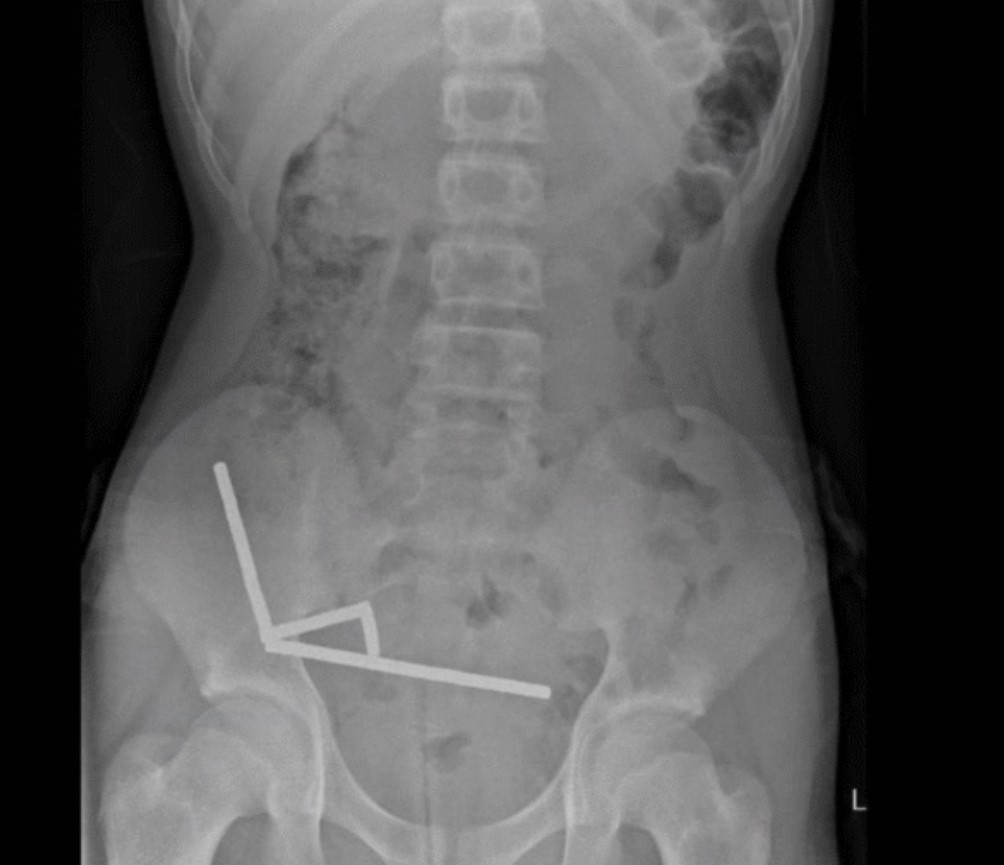

Хирурги провели операцию и обнаружили, что магниты находятся в разных отделах тонкой и слепой кишки. Соединяясь, магниты вызвали отмирание нескольких участков ткани из-за недостатка крови. Поэтому хирургам пришлось удалить часть кишечника мальчика. Несмотря на это подросток поправился и был выписан из больницы через восемь дней после операции.

магниты в кишечнике

Извлеченыне из кишечника магниты